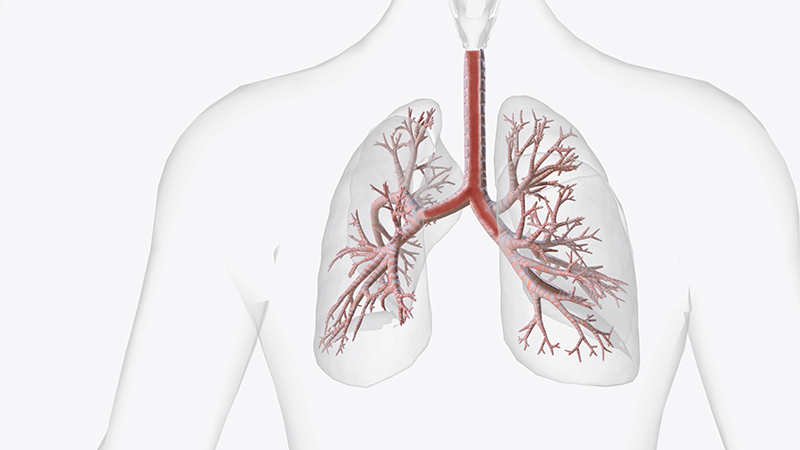

Рак бронхов относится к злокачественным новообразованиям, происходящим из наружного эпителия бронхов. Занимает 10-13 % от всех случаев онкопатологий и является одной из наиболее опасной, поскольку на начальных этапах своего развития она может протекать бессимптомно или с минимальными проявлениями.

Симптомы и признаки болезни

При таком заболевании как рак бронхов, симптомы на ранних стадиях часто схожи с обычными респираторными заболеваниями, тем самым часто затрудняя его своевременную диагностику. Они варьируются в зависимости от стадии заболевания и индивидуальных особенностей организма пациента.

Самый часто встречающийся признак рака бронхов — это постоянный кашель, который не проходит, несмотря на разные способы лечения. Кашель может сопровождаться выделением мокроты, иногда с примесью крови.

Другие проявления заболевания также могут включать в себя изменения в голосе, появление хрипоты, затруднение дыхания и учащенное дыхание. Пациенты могут испытывать боли в грудной клетке, ощущение сдавливания или дискомфорта. Со временем, при отсутствии адекватного лечения, возможно развитие общей слабости, усталости, потери аппетита и снижение массы тела.

Виды болезни

Выделяют несколько разновидностей бронхогенной карциномы, исходя из гистологической структуры клеток, формирующих опухоль и места ее расположения.

- Плоскоклеточный рак бронхов — формируется в бронхиальных структурах, находящихся к ближе к центру легких. Самый распространенная форма, ее доля составляет 60% от всех случаев злокачественных опухолей дыхательных путей.

- Аденокарцинома бронхов — разновидность немелкоклеточного рака, начинающаяся в железистых клетках мелких бронх и бронхиол.

- Крупноклеточный нерасслоенный рак характеризуется большими клетками, формирующимися в любой части легких.